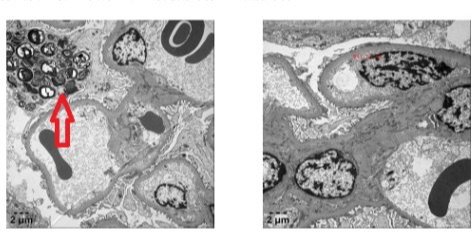

2023年11月,两例疑似法布雷病患者在新疆医科大学第一附属医院肾病中心就诊,经肾组织穿刺病理及基因诊断最终确诊为法布雷病。这是新疆肾脏病专业首次诊断遗传基因、临床及肾组织病理资料齐全的法布雷病患者,标志着新疆医科大学第一附属医院肾脏疾病中心对于疑难病、罕见病诊疗技术达到国内先进水平,诊治水平再上新台阶。法布雷病(Fabry disease)是一种X染色体伴性遗传的溶酶体贮积症,α-半乳糖苷酶A基因突变导致该酶活性....查看详情 >